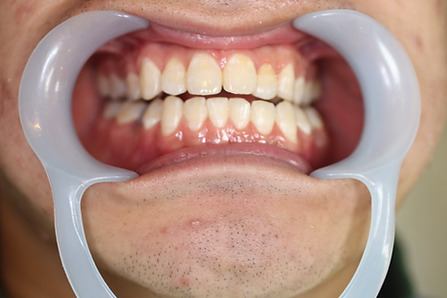

2ホワイトニング【治療例1】

治療前

治療後